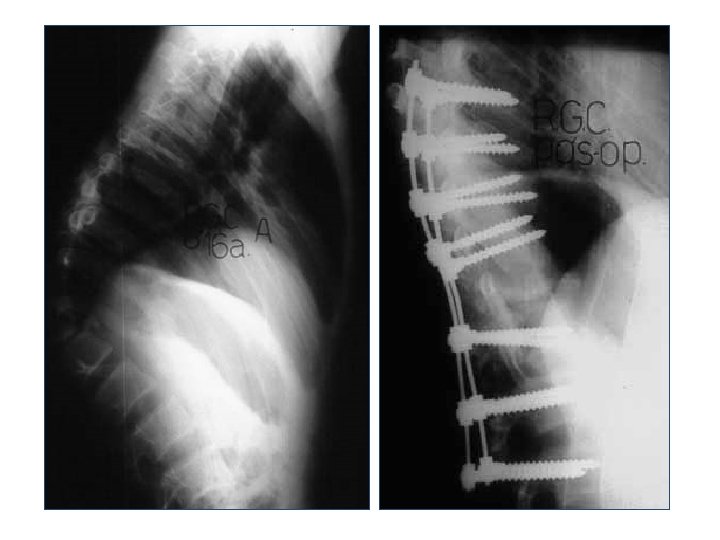

Radiografia

Radiografia Lateral Anteroposterior Alinhamento Altura dos corpos Desvios

Tratamento Objetivos • Descompressão • Melhora da função neurológica • Alinhamento • Reabilitação